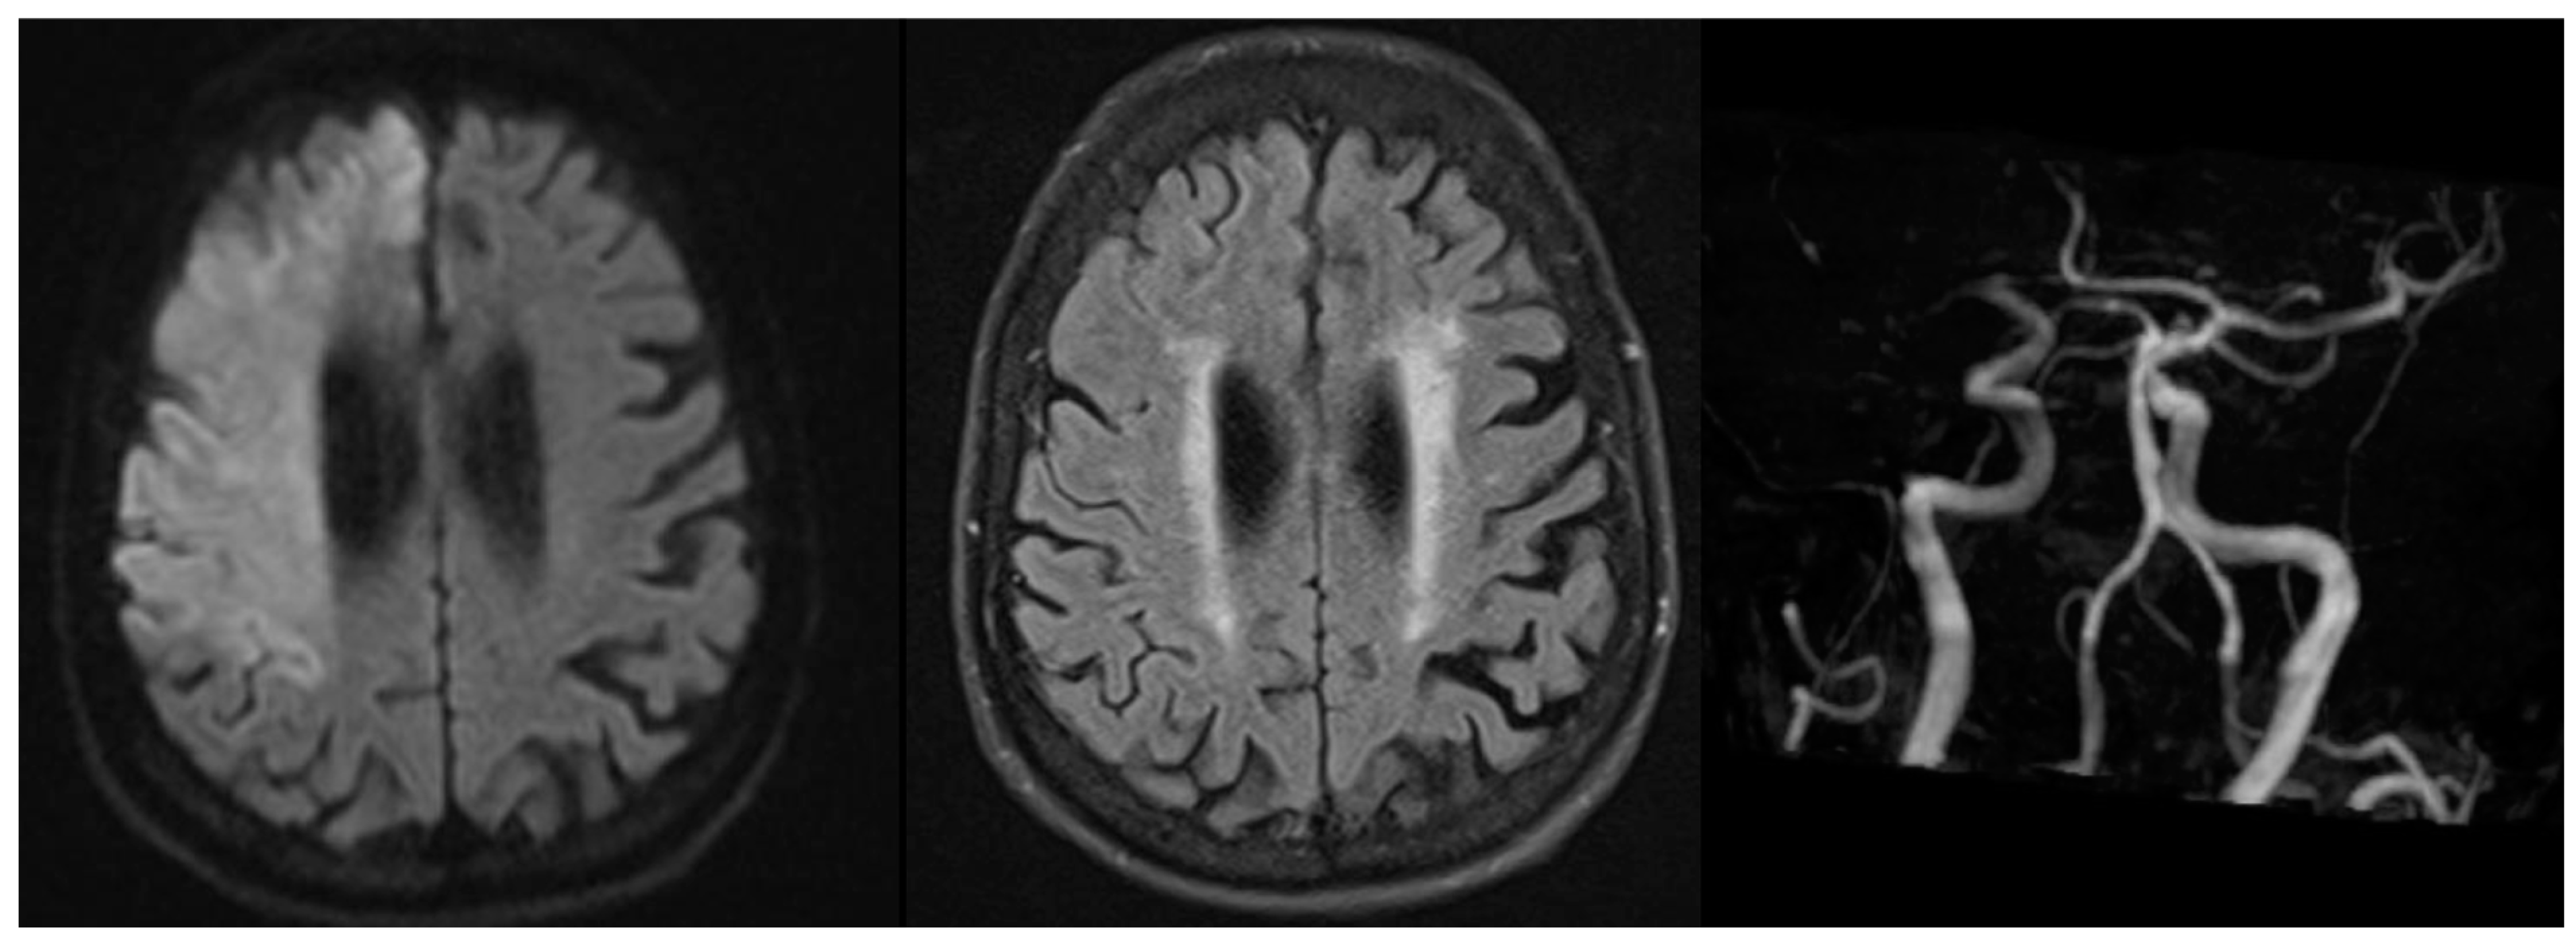

5. Non-Advanced Imaging for Wake-Up Stroke